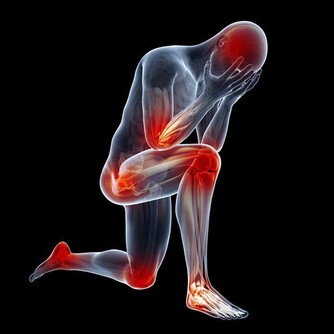

高脂血症容易導致血液黏稠,誘發炎症反應,形成動脈粥樣硬化,對腎臟造成損害;高血壓患者,腎臟的血管就會承受更多的壓力,長期下去,血管就會硬化,腎臟也會硬化;高尿酸的肥胖患者易形成結石,腎臟成為被攻擊器官之一,此外高尿酸血症也容易引發炎症反應、高血壓、高血脂等。